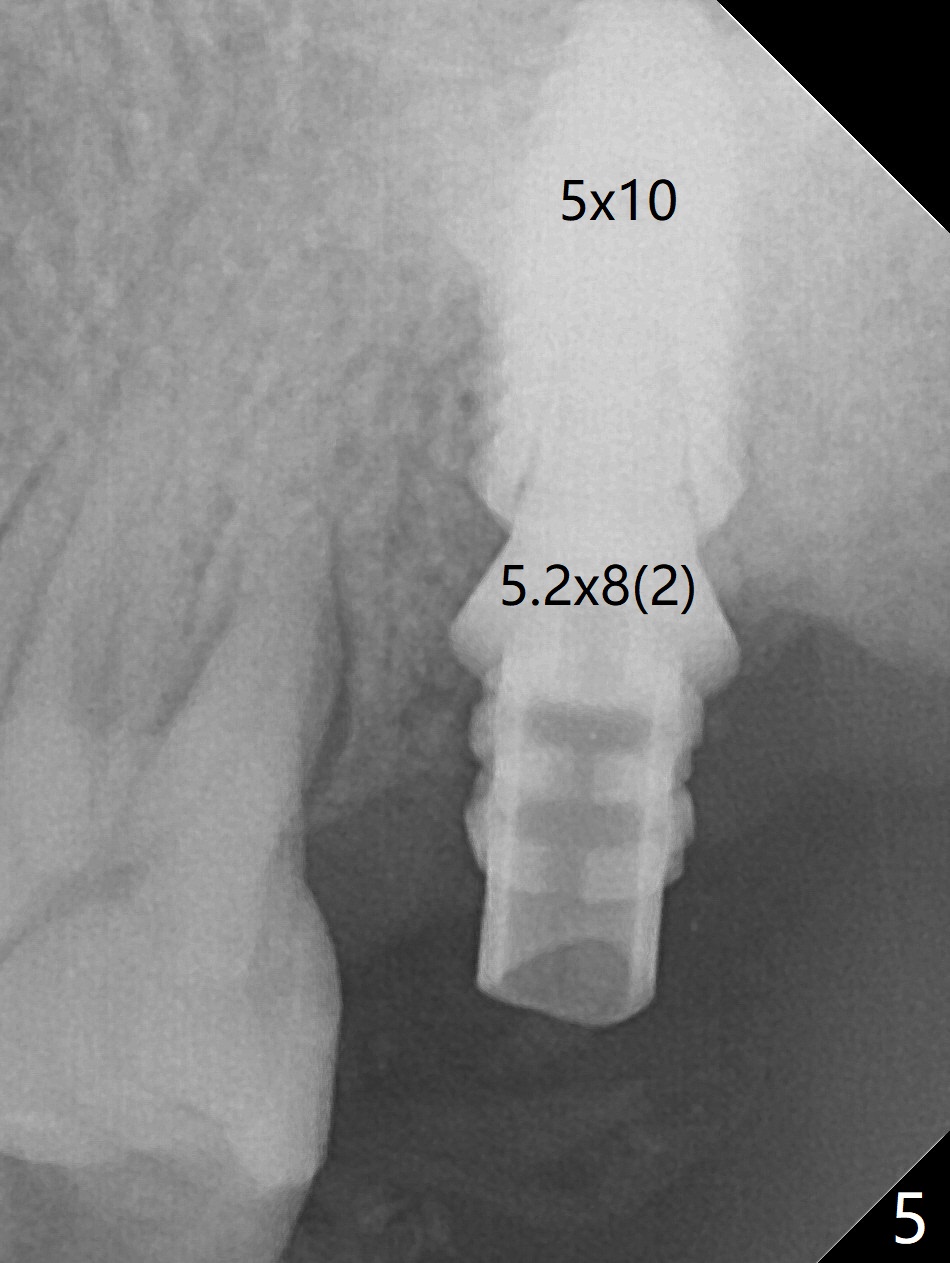

Although the buccal (Fig.1 (mesial view of the extracted tooth #15): B) root is larger than the palatal (P) one, the palatal socket is larger than the buccal one (Fig.2 white area) because of the bone loss of the former. For better restoration, osteotomy (Fig.2 red line) is initiated in the buccal slope of the septum (S) so that the final osteotomy is in the middle of the whole socket (Fig.3 red box). In fact a 3 mm stopper is not used because of the slope and the clumsy stopper. Stopper would be indicated if the bottom of the bone were flat. At first a 4x10 mm dummy implant is placed with stability (Fig.4). After further osteotomy and sinus lift (Fig.6 red dashed line: sinus floor), a 5x10 mm implant is placed with 30 Ncm, followed by insertion of a 5.2x8(2) mm temporary abutment (Fig.5,6). The latter holds an immediate provisional and Vanilla Graft/Osteogen (Fig.7 *) in place (^: distal crestal bone). Although the bone looks normal around the implant 7.5 months postop (Fig.4), the implant is unstable, probably due to the large preexisting defect. In contrast the implant placed at the healed site of #3 is stable 6.5 months postop. The 8x5 mm healing abutment that dislodged for 1 day could not return. A 6x5 mm one is used; it appears that the bone density mesial and distal to the implant is low (Fig.9 *). The implant looks normal and is stable 13 months postop (Fig.10). A 5.7x5.5(5) mm cementation abutment is placed for a provisional (progressive loading, Fig.11). There is no pain associated with the provisional for mastication. Impression is taken 7 days later. The patient has pain when the permanent crown is cemented. It appears that the implant does not osteointegrate and should be removed. A 6x14 mm tissue-level implant will be immediately placed following a 5 and 6x14 mm taps and bone graft and PRF (Metronidazole). In fact there is no pain when the existing abutment is torqued at 35 Ncm 1 year 8 months postop (Fig.12). The mesiogingival portion of final restoration (Fig.13 arrowheads) should be bulky so that the gingival embrasure (red dashed line) is minimal to reduce food impaction.